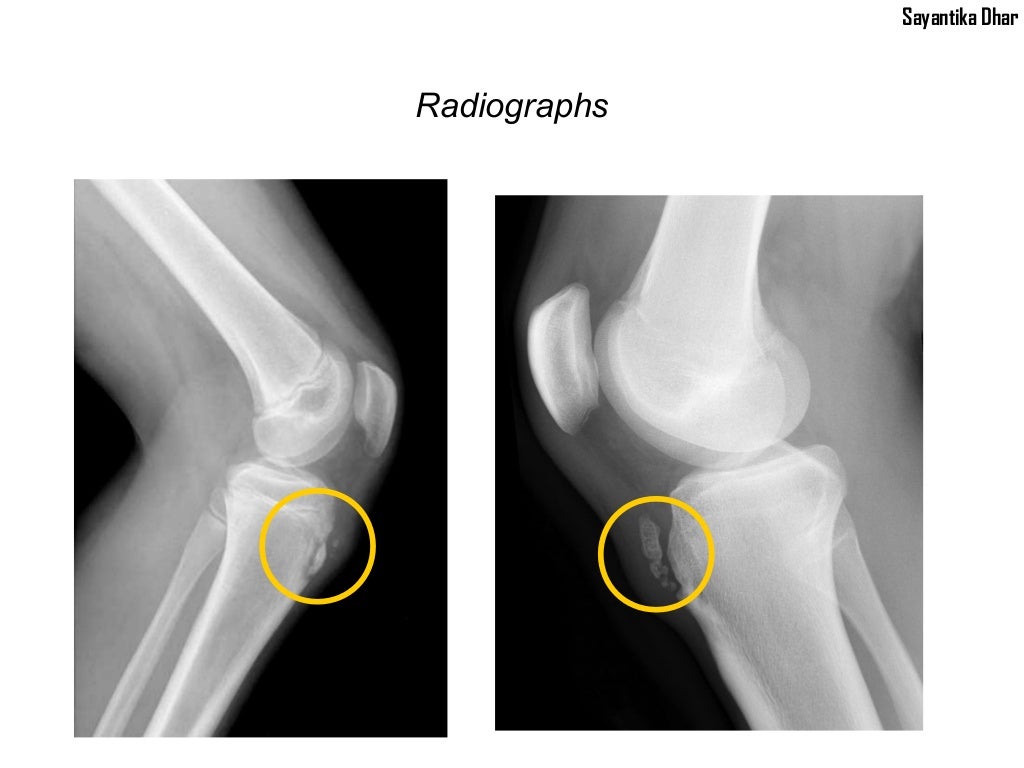

From www.slideserve.com

PPT Osgood Schlatters Disease PowerPoint Presentation, free download Icd 10 Code For Osgood Schlatter Disease Right Knee It is an inflammation of the area just below the knee where the tendon from. osgood schlatter disease, also known as osteochondrosis or traction apophysitis of the tibial tubercle, is a common cause of anterior knee. Reimbursement claims with a date of service on or after october 1,. icd 10 code for juvenile osteochondrosis of tibia tubercle. . Icd 10 Code For Osgood Schlatter Disease Right Knee.